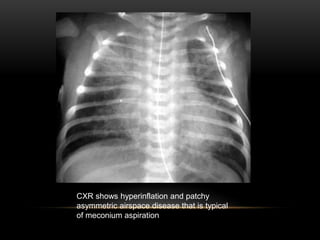

CXR shows hyperinflation and patchy

asymmetric airspace disease that is typical

of meconium aspiration

• The radiology of meconium aspiration reflects the underlying pathophysiology. The

aspirated meconium results in complete obstruction of the bronchi, resulting in

atelectasis and compensatory hyperinflation of the remaining patent airways. Overall

the lungs appear hyperinflated. Barotrauma is a frequent complication.